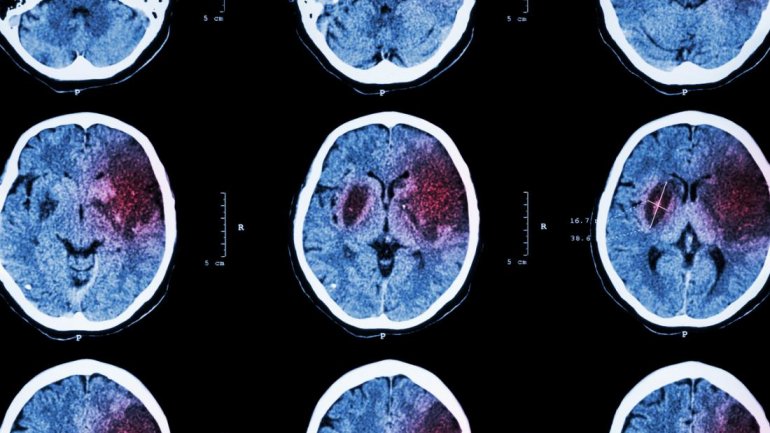

Η απάντηση της AstraZeneca για τον κίνδυνο εμφάνισης θρομβώσεων μετά το εμβόλιο

Η AstraZeneca Plc ανακοίνωσε σήμερα ότι πραγματοποίησε έλεγχο σε ανθρώπους που έχουν εμβολιαστεί με το εμβόλιό της κατά του Covid-19, ο οποίος έδειξε ότι δεν υπάρχουν....